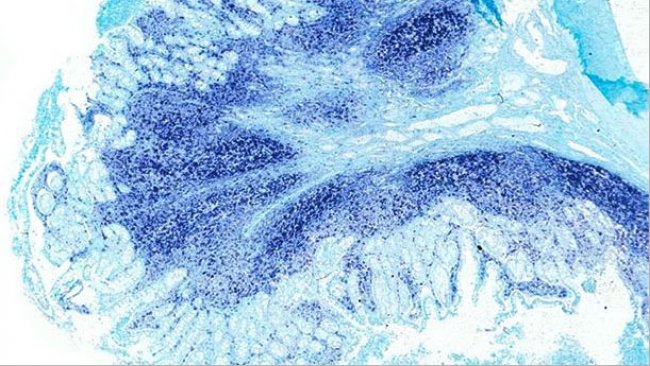

Recently, PCV2 has been suggested as a pathogen able to induce diarrhoea in pigs, and PCV2-enteric disease (PCV2-ED) as a separate entity within porcine circovirus diseases (PCVDs) has been proposed.